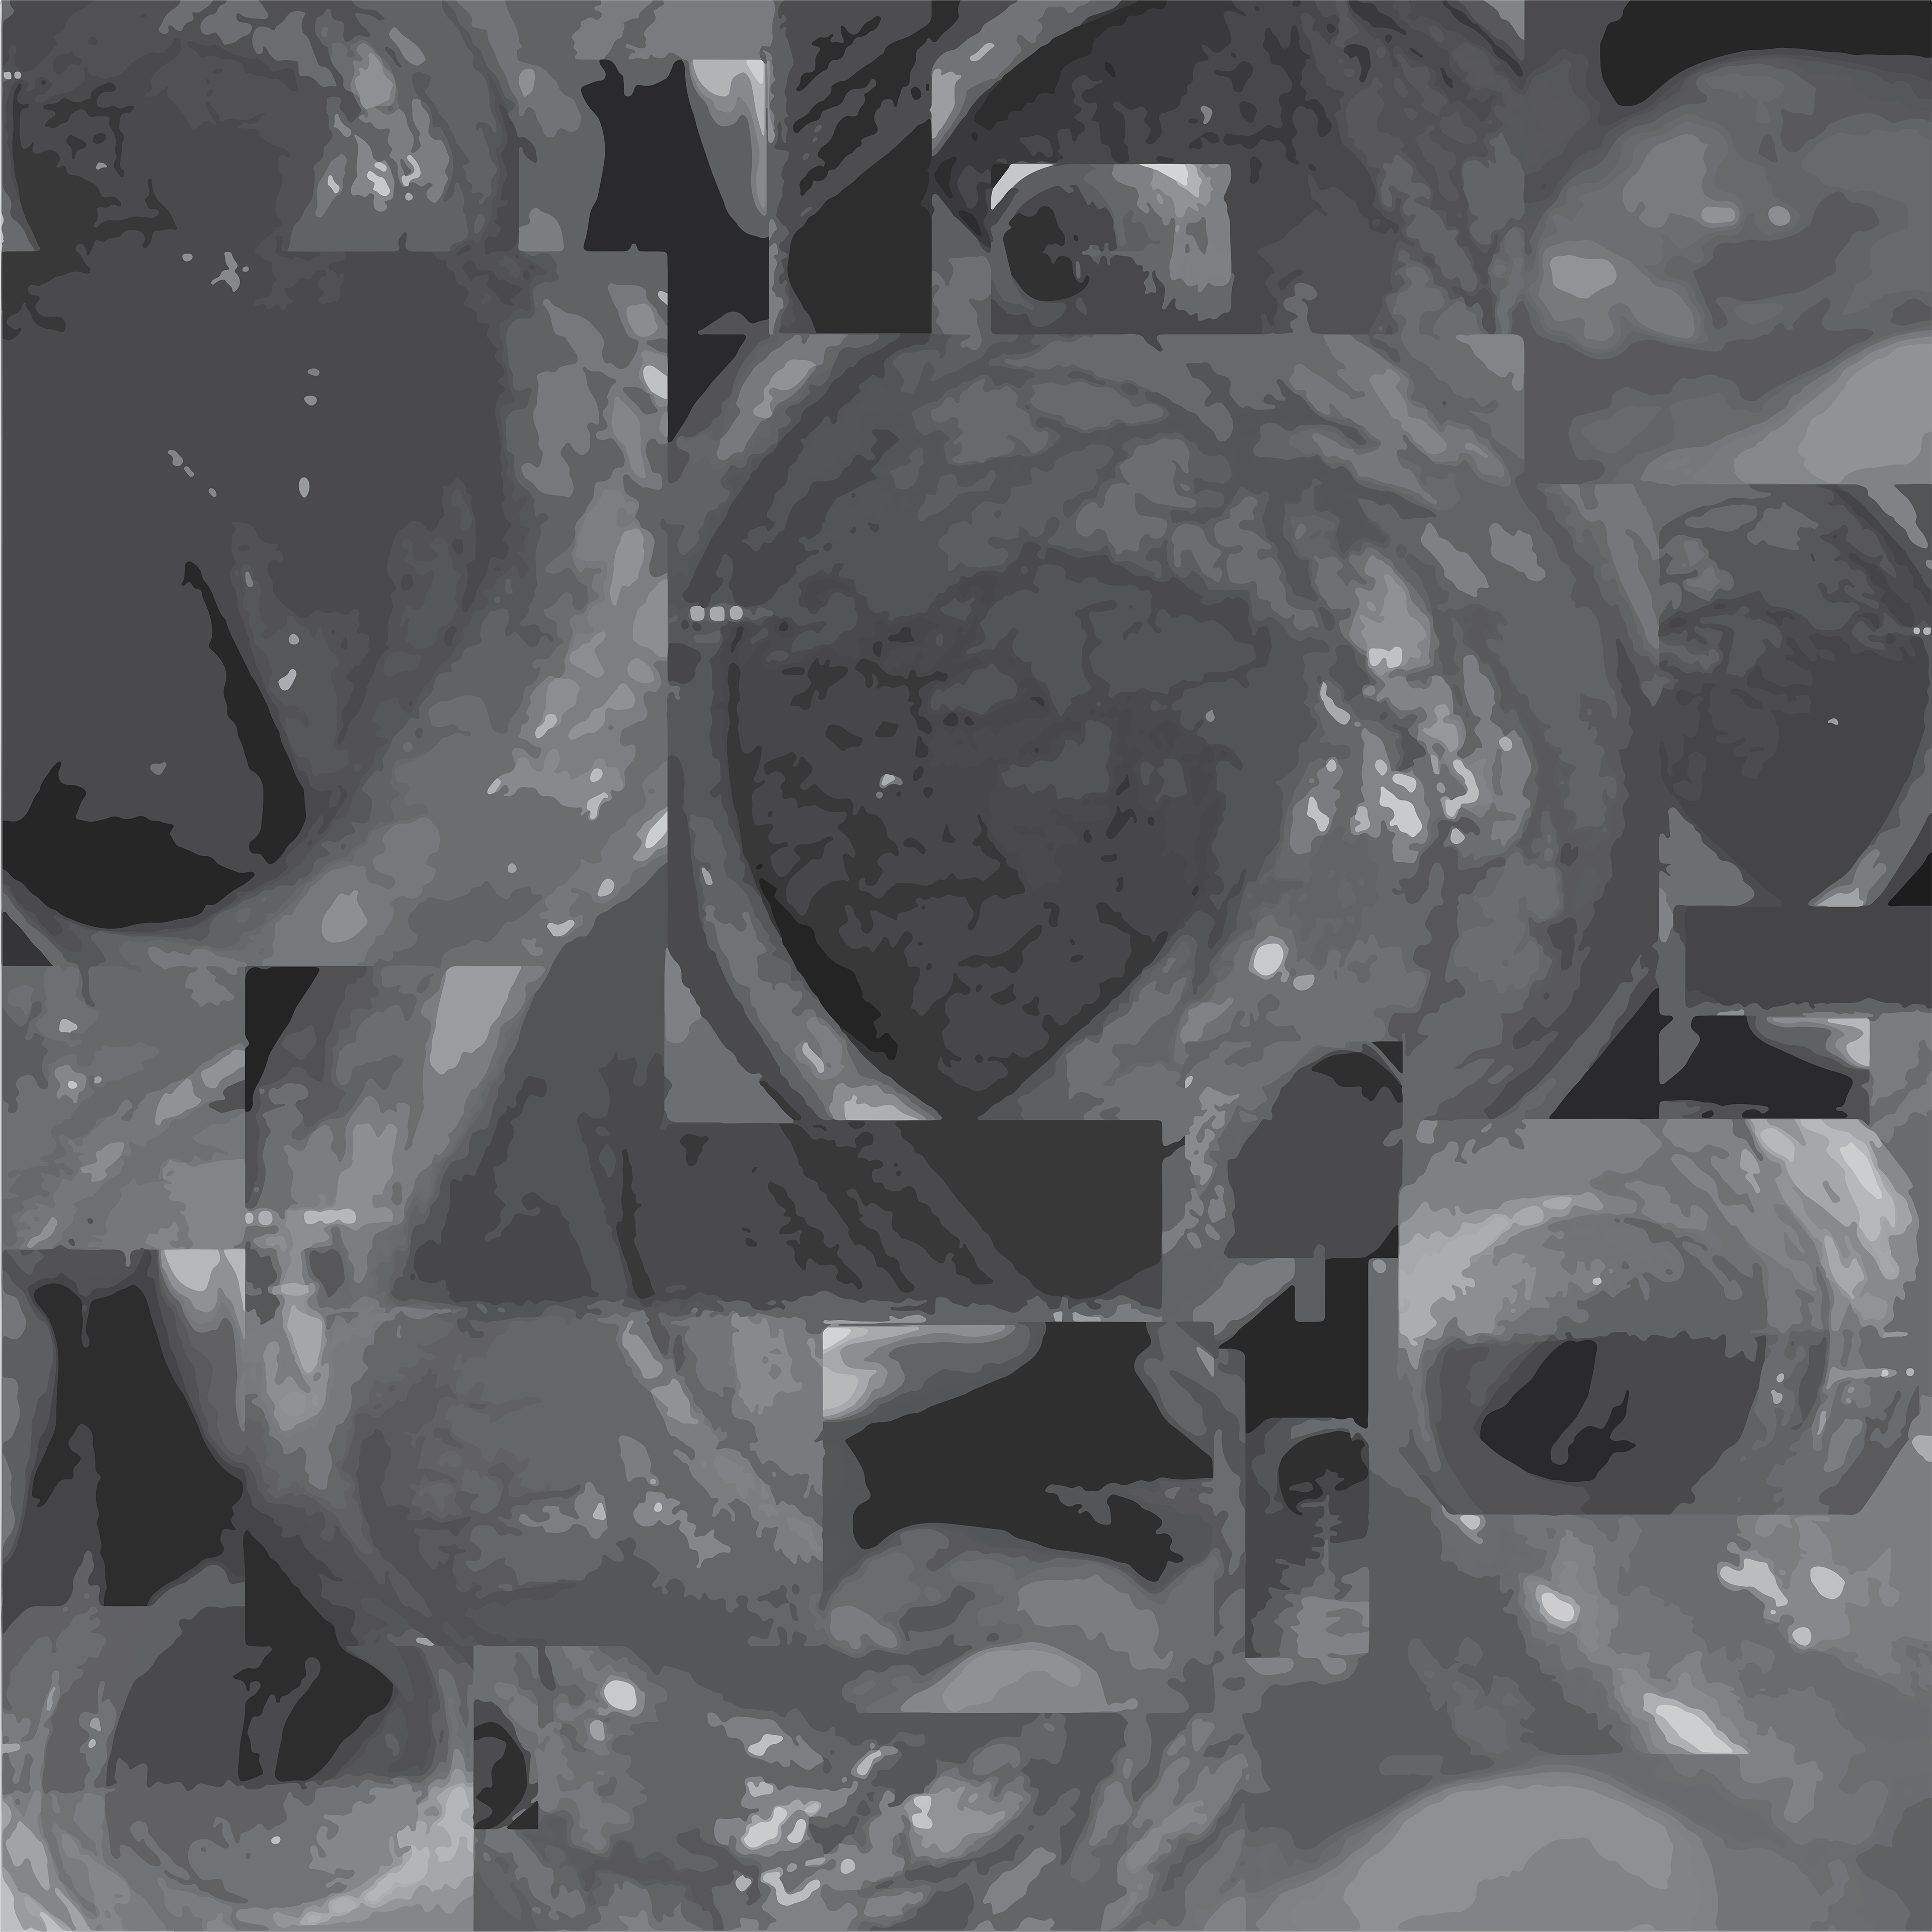

The next step was to produce a fleshed out collage (no pun intended) centered on the previous iteration. This collage was then turned to grayscale and separated by darkness into 13 layers.

The layers were then individually manipulated as the original rendering of the Chichu negative geometric spaces.

Each image was layered in a single document and restrained with a clipping mask using the respective original grayscale layer.